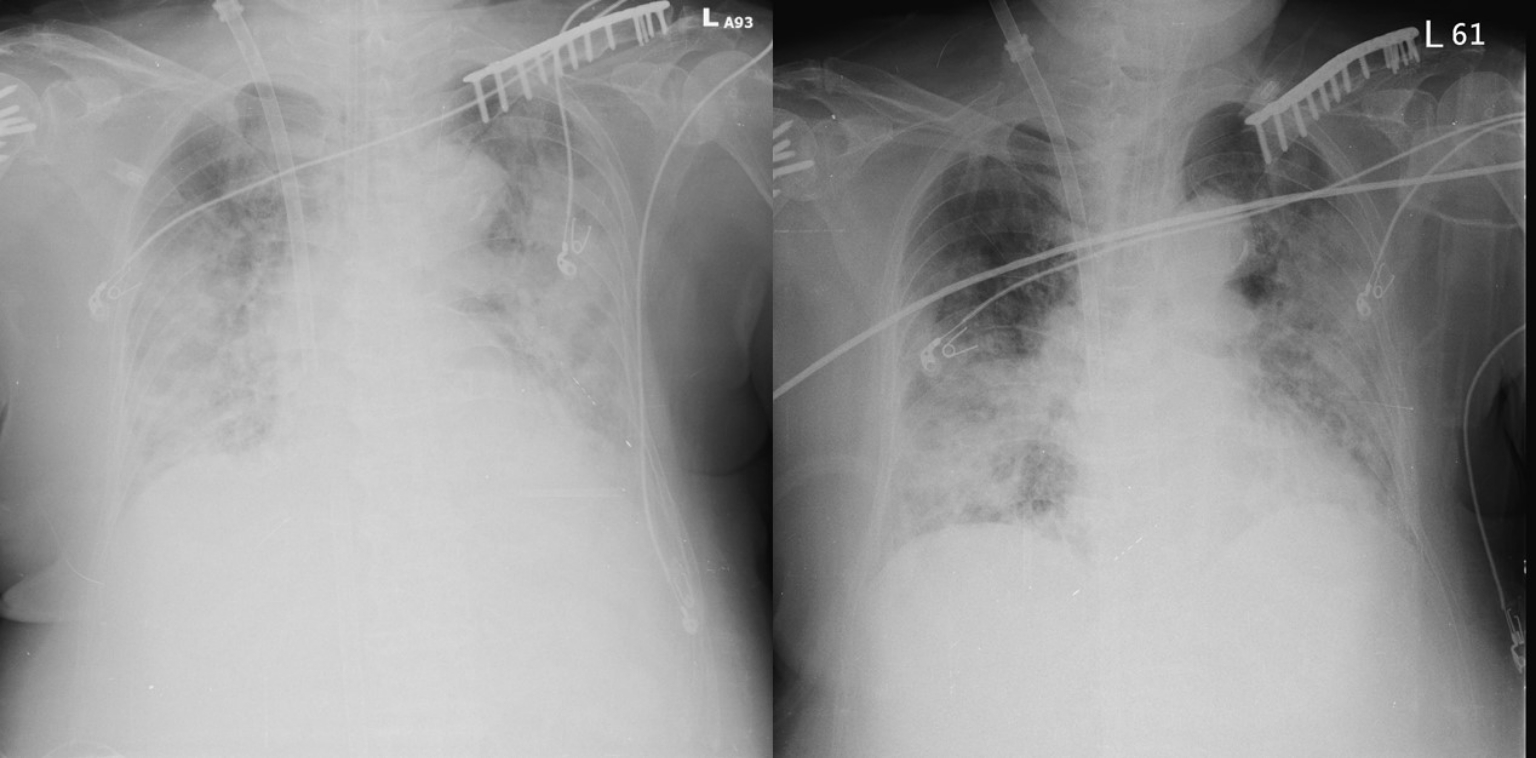

問到這位老婦人當時的狀況,台北榮總過敏免疫風濕科主治醫師廖顯宗說明,「這個病人之前有使用2-3個禮拜的強效抗生素,因為治療效果不是那麼好,後來一個病毒感染產生身體細胞激素的風暴,影響到心、肺和血壓,在經過討論後使用抗IL-6的抑制劑,用完後發現她的X光在一天內就改善非常多。」

蔡長祐用X光解釋,「X光片像底片的負片一樣,密度越濃越硬就會越白,越透光的部分會越黑,所以看到肺部X光片是黑的、大部分是空氣,就像一個海綿,但發炎的時候細胞會跑來這裡會產生水份就會局部水腫,密度就會增加變白,等到整個肺部變白了後表示裡面水份很重、細胞成分很重,是一個嚴重發炎的狀況。」

廖顯宗補充,這名患者打的劑量是根據體重來算,「那時候是用體重1公斤打8毫克來算,婦人大約70公斤,所以打了560毫克,一天分2次把劑量打完,打完隔天照X光肺部浸潤狀況就改善非常多。」